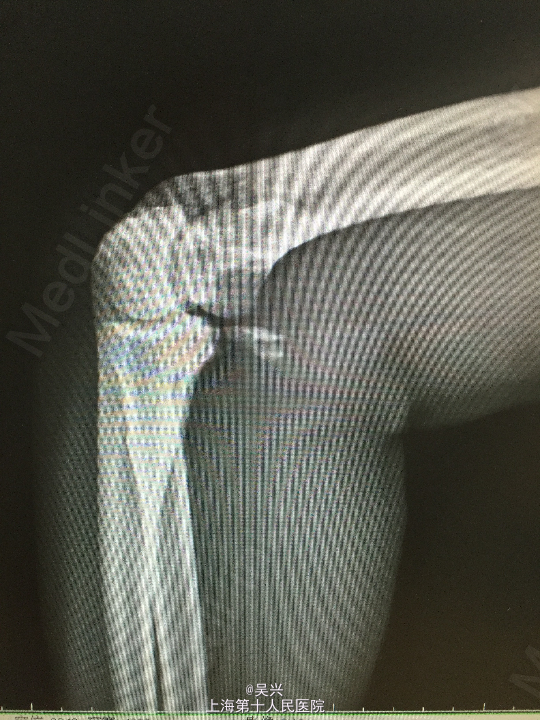

左肘外伤肿痛畸形3小时。左肘屈曲位着地受伤。

急症查体见肘关节肿胀、触痛,存在向后方半脱位及外侧松弛不稳定。

诊断:左肘恐怖三联症。 处理:术前准备,抗炎消肿治疗,术后三天行左肘正中切口显露尺骨冠状突,术中见尺骨冠状突粉碎性骨折,用两枚微型空心螺钉固定,发现屈肘位置仍有肘关节半脱位趋向。予伸肘位石膏固定,术后2周改屈肘45度位石膏固定,术后4周拆石膏,能逐渐屈肘至90度。

随访:术后1月患者肘关节稳定性良好,伸肘0度,屈肘90度,理疗辅助功能锻炼中。 讨论:肘关节脱位(半脱位)伴尺骨冠状突骨折、桡骨小头骨折称为肘关节恐怖三联症。该症存在极度肘关节不稳定,容易发生向后方、侧方脱位。一般单纯尺骨冠状突骨折极少,多伴有桡侧结构损伤和关节不稳定。肘关节恐怖三联症治疗原则一般是复位固定尺骨冠状突和桡骨小头,修复桡侧副韧带。我们术中发现固定尺骨冠状突后关节仍然不稳定,但桡骨小头因不全骨折需要石膏固定,因此不采取手术修复外侧副韧带,而是石膏固定,术后也取得较好的效果。